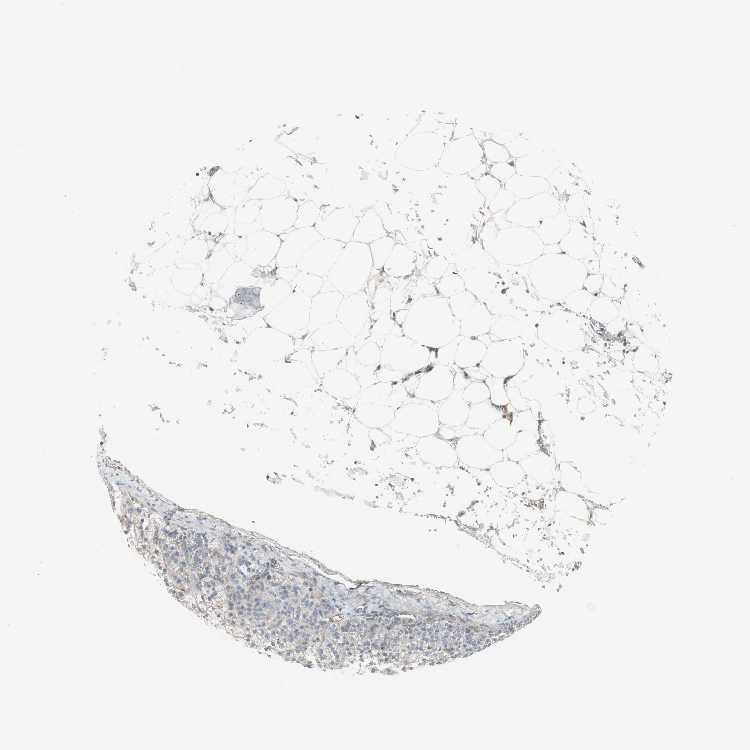

ADRENAL GLAND - Antibody stainingi

Antibody staining in the annotated cell types in the current human tissue is reported as not detected, low, medium, or high, based on conventional immunohistochemistry profiling in selected tissues. This score is based on the combination of the staining intensity and fraction of stained cells.

Each image is clickable and will lead to virtual microscopy that enables deeper exploration of all samples and also displays staining intensity scores, fraction scores and subcellular localization as well as patient and tissue information for each sample.

Antibody HPA005758

Glandular cells Not detected